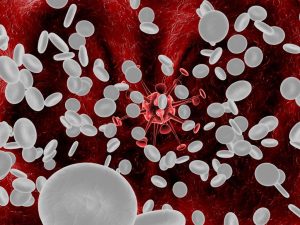

La leucemia es un tipo de cáncer de la sangre que comienza en la médula ósea, el tejido blando que se encuentra en el centro de los huesos, donde se forman las células sanguíneas.

La leucemia lleva a un aumento incontrolable de la cantidad de glóbulos blancos.

Las células cancerosas impiden que se produzcan glóbulos rojos, plaquetas y glóbulos blancos maduros (leucocitos) saludables. Entonces, se pueden presentar síntomas potencialmente mortales a medida que disminuyen las células sanguíneas normales.